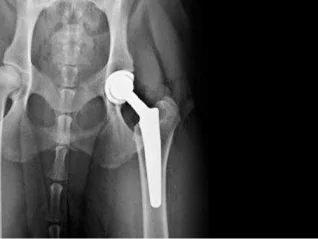

Total Joint Replacement